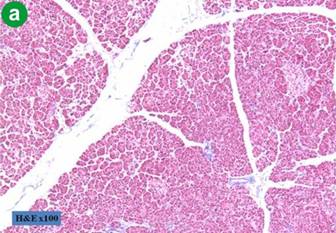

Assessment of Pancreas Consistency

In all cases, pancreatic duct diameter was measured after pancreatic transection by the operator. Parenchyma texture was divided into two groups based upon the extent of fibrotic changes in the resection margin. A fibrotic change was assessed by trichrome staining. Soft pancreatic parenchyma was characterized by the absence of fibrosis or slight thickness of perilobular fibrosis (up to 50 μm). Hard parenchyma was characterized by thick perilobular fibrosis greater than 50 μm (Figure 1).

Figure 1. Results of trichrome staining on the resection margin of the pancreas. a. b. Absence of fibrosis or slight thickness of perilobular fibrosis (less than, or equal to,50 μm ). c. d. Hard parenchyma was characterized by thick perilobular fibrosis greater than 50 μm. The purple color stained by trichrome show the component of fibrotic change in perilobular space. |